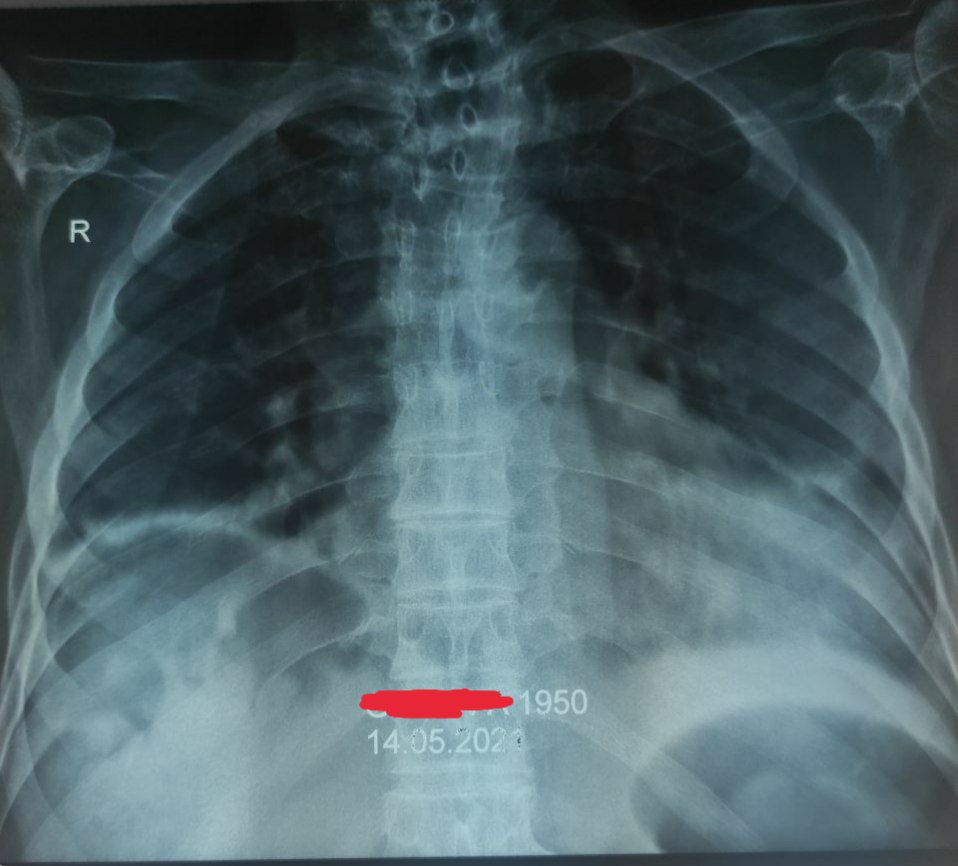

Со слов больного страдает гипертонической болезнью

Тяжело перенес covid 19

В данный момент: затруднение при дыхании, ортопное, болезненность в грудной клетке

Давление низкое

Сатурация низкая

И у него тахикардия